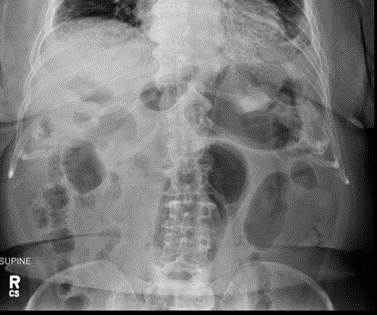

Surgical findings included gastric erosion at the gastroesophageal junction and a large hiatal hernia with most of the stomach in the chest cavity. The stomach and mediastinal tissue planes were relatively edematous. The stomach was reduced from the thoracic cavity as much as possible. A laparoscopic Nissen fundoplication was performed to hold the stomach in the correct orientation within the abdominal cavity. There were no complications during the procedure. She was given prophylactic heparin and perioperative IV cefazolin. The patient recovered quickly from surgery. The post-operative chest x-ray and swallow study were normal. The patient did present to the ED several days postoperatively with pleuritic right mid back pain post coughing, but workup was negative. At that time, the abdominal surgical incisions were noted to be well healing and the patient reported normal bowel movements on a full-liquid diet. There were no other complications [Figure 1-3].

Initial radiography usually reveals a herniated stomach above the diaphragm, with air fluid levels seen inside the stomach. A chest X-ray may show a retrocardiac gas-filled viscus that can help confirm the diagnosis. Abdominal imaging may reveal a distended viscus in the upper abdomen. An organ axial volvulus may show a horizontal orientation of the stomach with a single air-fluid level and a paucity of distal gas [3]. A mesenteroaxial volvulus may show plain abdominal plain radiographic findings showing a spherical stomach on supine images with two air-fluid levels on erect images with the antrum positioned superior to the fundus [3]. Endoscopy is also used in the evaluation and treatment of a patient with gastric volvulus. Endoscopies are sometimes used to evaluate upper abdominal issues and as a result can reveal signs of gastric volvulus as a byproduct [12].